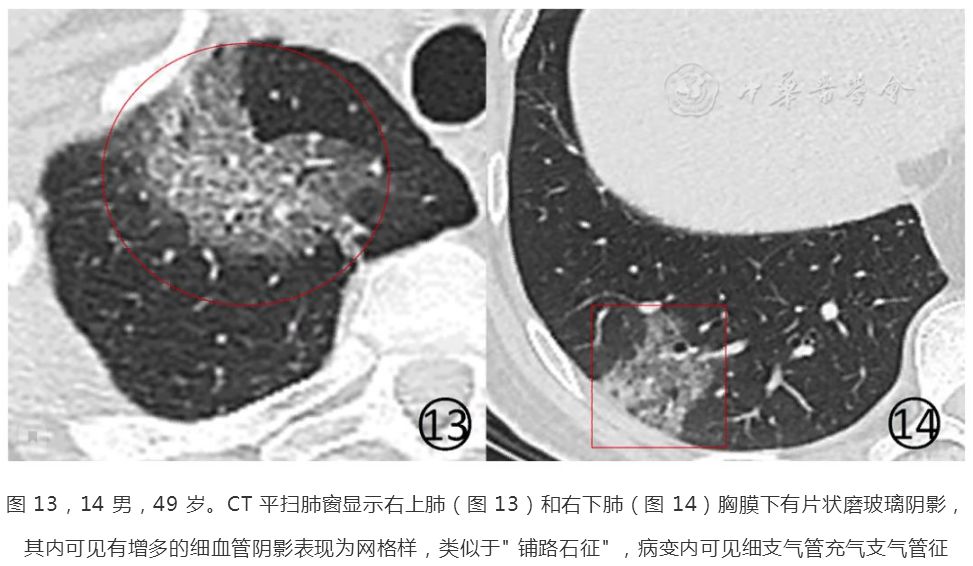

再来看这个新冠肺炎患者,磨玻璃阴影内有清晰的网格状阴影,类似铺路石征。

图9